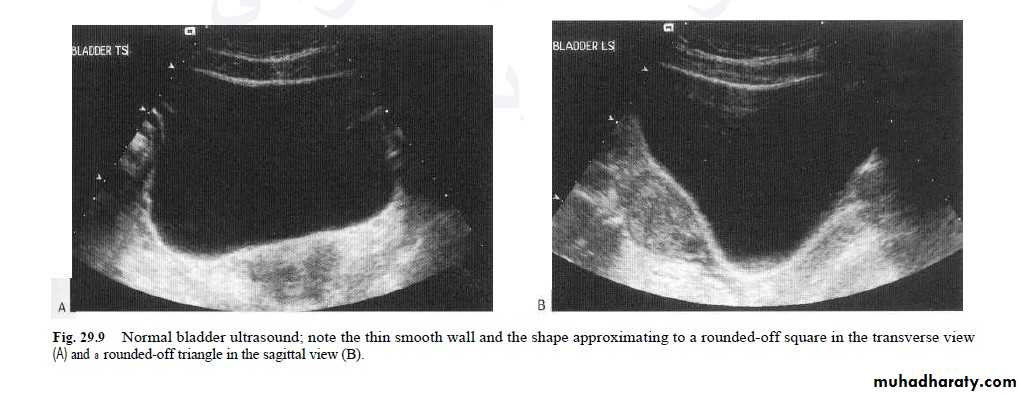

Urinary bladderThe bladder is well demonstrated on all imaging modalities. At US, the simplest routine method of imaging, the bladder lumen should be free of echogenic structures and it's wall should be of uniform thickness. When the bladder is distended, the wall should be less than 3 mm thick. The volume of the bladder may be calculated by measuring the dimensions of the bladder